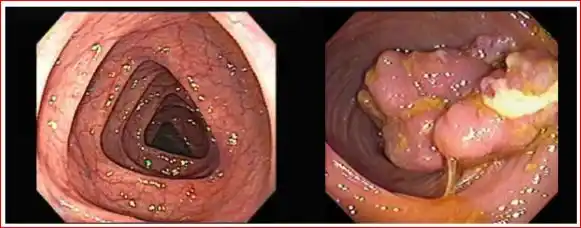

PÓLIPOS EN EL COLON

El cáncer de colon es causado por un crecimiento anormal en la mucosa colónica y el

recto. Esas anomalías se denominan pólipos que pueden seguir creciendo y extenderse

dentro del colon o, incluso, invadir otros órganos del cuerpo cuando ya es un cáncer.

La colonoscopía es el método más eficaz para detectar pólipos y lesiones en el colon.

Gracias a esta tecnología, se pueden identificar pólipos muy pequeños que, en la

mayoría de los casos, pueden extraerse en la misma intervención, evitando su

progresión a cáncer.

¿Qué es una colonoscopia?

Es un examen que permite la visualización directa del intestino grueso (colon y recto) y

se realiza con un equipo flexible y delgado que se introduce por el ano y que tiene una

cámara en su extremo que permite obtener imágenes y videos que se transmiten a un

monitor.

¿Qué puede detectar una colonoscopia? La colonoscopia posibilita la prevención del

cáncer de colon y recto porque permite encontrar y sacar los pólipos adenomatosos. Los

pólipos o adenomas son crecimientos anormales de las células en la pared interna del

intestino que crecen lentamente y pueden transformarse en un cáncer sino se detectan y

sacan a tiempo. La colonoscopia también posibilita la detección del cáncer colorrectal

en etapas tempranas.